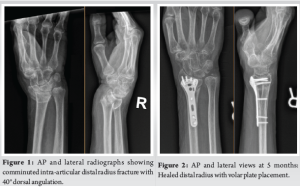

A 62-year-old left-hand dominant female presented to the emergency department after sustaining a ground-level fall with complaints of right wrist pain and right pelvic pain. Initial radiographs revealed an intra-articular comminuted distal radius fracture with approximately 40º of dorsal angulation (Fig. 1). The patient also sustained a right-sided complete sacral fracture, right anterior column acetabular fracture, right inferior rami fracture, and a left parasymphyseal rami fracture. Treatment options were discussed with the patient, and the patient elected to undergo operative intervention of both the wrist and pelvis by an orthopedic traumatologist.

A standard volar approach was made over the flexor carpi radialis (FCR) tendon. Two separate intra-articular fragments were identified: A radial styloid component and a lunate facet component. A volar distal radius locking plate was used to provide primary fixation. The patient was placed in a volar-based splint. During the same anesthesia event, the patient underwent operative fixation of pelvis fractures as well. The patient was compliant with physical therapy protocols for distal radius fracture and pelvis fractures. Five months after the index injury, the patient presented to the orthopedic trauma clinic with acute inability to flex the right thumb without an inciting event. The patient was subsequently referred to the senior author for further management. Radiographs at that time revealed a well-healed distal radius fracture with plate placement on the volar rim (Fig. 2). Examination revealed inability to flex the thumb IP joint, with a lack of tenodesis effect, which confirmed atraumatic FPL rupture. Treatment options were discussed, and the patient elected to undergo removal of hardware and FPL tendon reconstruction with PL interpositional graft. The operation began with a standard volar approach over the FCR tendon. The proximal FPL tendon stump was found to be completely ruptured and the surrounding tenosynovium was sharply excised. There was an excellent excursion of the proximal FPL muscle belly, which was found to be >2 cm. The median nerve was found to be adherent to the FPL and was subsequently neurolyzed. The previously placed plate and screws were removed and fluoroscopic imaging confirmed a well-healed fracture. An incision was made over the thumb in a Brunner-like fashion. The A1 pulley was released. The distal FPL tendon stump was then pulled through the wound (Fig. 3). A 15 cm length of PL tendon was harvested. The PL tendon autograft was secured using a Pulvertaft weave technique into the distal portion of the FPL tendon and reinforced with 3-0 braided polyester suture (Fig. 4). The tendon was delivered through the palm and out through the forearm incision. The wrist was held in neutral position while appropriate tension was placed and a first proximal Pulvertaft weave was placed. The wrist was taken through a full range of motion and appropriate tension was confirmed (Fig. 5). The thumb maintained 5° of flexion with full wrist flexion. The patient was placed in a thumb-based dorsal blocking splint and made non-weight bearing with the right upper extremity.